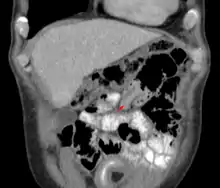

| An intussuception as seen on CT | |

An intussusception is often suspected based on history and physical exam, including observation of Dance's sign. A digital rectal examination is particularly helpful in children, as part of the intussusceptum may be felt by the finger. A definite diagnosis often requires confirmation by diagnostic imaging modalities. Ultrasound is the imaging modality of choice for diagnosis and exclusion of intussusception, due to its high accuracy and lack of radiation. The appearance of target sign (also called "doughnut sign" on a sonograph, usually around 3 cm in diameter, confirms the diagnosis. The image seen on transverse sonography or computed tomography is that of a doughnut shape, created by the hyperechoic central core of bowel and mesentery surrounded by the hypoechoic outer edematous bowel.[10] In longitudinal imaging, intussusception resembles a sandwich.[10] It is also called "pseudokidney" sign because hyperechoic tubular centre is covered by a hypoechoic rim producing a kidney-like appearance.[11]